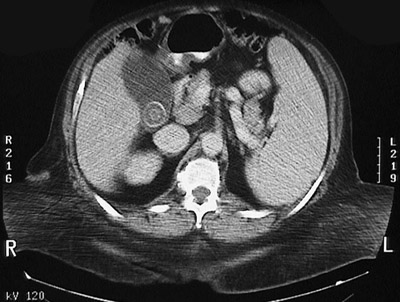

![]() | This abdominal CT scan with contrast demonstrates a gallstone within a dilated gallbladder next to the liver on the patient's right. Gallstones may contain varying portions of cholesterol, calcium, and bilirubin. They are often built through apposition of layers, leading to the laminated appearance seen here. |